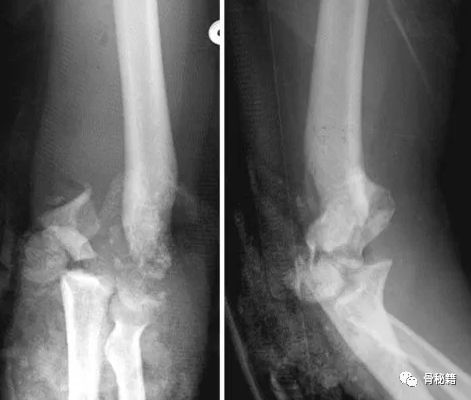

说到复位的细节,就要了解肱骨远端的解剖

1.解剖中比较重要的就是柱的概念,分为外侧柱和内侧柱,一个重要的滑车结构包含了300度的关节面,在外侧有一个肱骨小头的结构,然后一个冠突窝的结构

2.其中有几个重要的角度,4-8度的轻微外翻角,30度前方的前倾角

肱骨的内外侧柱和滑车构成了一个三角形稳定结构,手术复位的时候一定要完成稳定三角结构的恢复。

前倾角通常在临床中容易被忽略,因为我们是从后方进行手术,对前倾角度无法进行直接的观察。

前倾角从内侧和外侧观察,角度也不太一样需要注意,内侧大约10-20度,外侧大约30-40度。

前倾角度的复位不良可能造成肱骨的屈伸功能下降,在侧位的时候一定需要注意。

该例患者的前倾角就没有较好的恢复